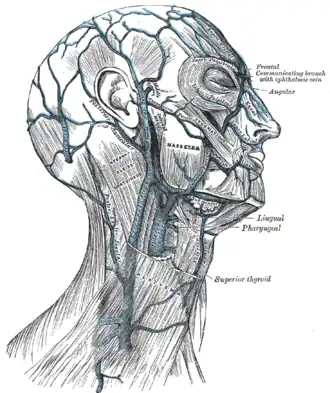

On both sides of the scalp, there are five large arteries that perfuse the scalp. Local flaps used for scalp reconstruction must contain at least one of these major arteries, to maintain a reliable blood supply. The scalp can be divided into four different vascular territories:

- Anterior: supratrochlear artery and supraorbital artery

- Lateral: superficial temporal artery

- Posterior: occipital artery

- Posterolateral: posterior auricular artery[4][7]

The veins anastomose frequently with each other and enter the diploic veins of the skull bones and the dural sinuses. This is an extra difficulty as the vein pattern differs. The scalp veins accompany the arteries and have similar names:

- Anterior: Supratrochlear vein and supraorbital vein

- Lateral: Superficial temporal vein

- Posterior: Occipital vein

- Posterolateral: Posterior auricular vein